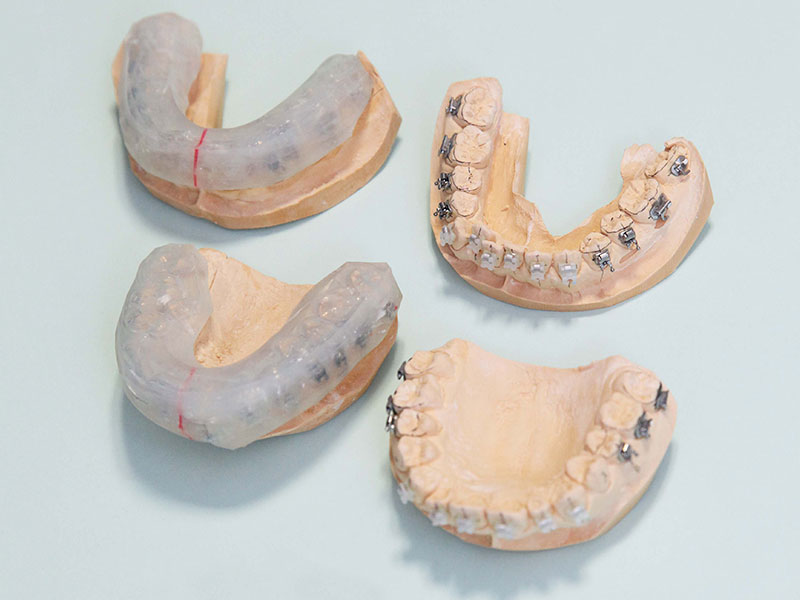

3、インダイレクトボンディング

当院では、インダイレクトボンディング法 (間接接着法)を取り入れています。

インダイレクトボンディング法とは、ブラケット(ワイヤーを通すために歯に装着する装置)を模型上に正確に位置づけし、専用のトレーを用いて装着する方法です。

当院では、目立ちにくいセラミックのブラケットを使用しています。